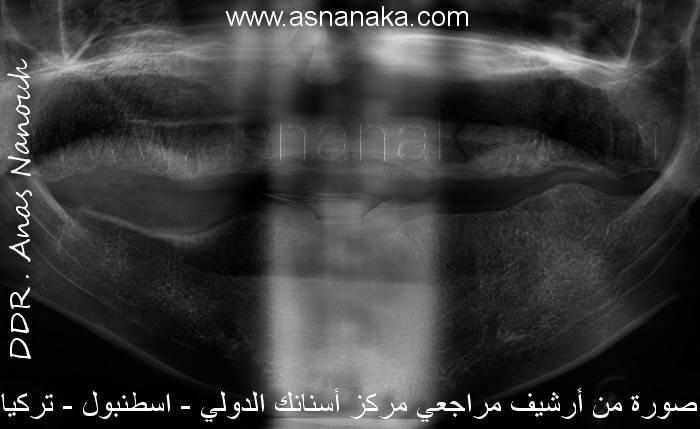

| حالة زراعة أسنان صعبة |